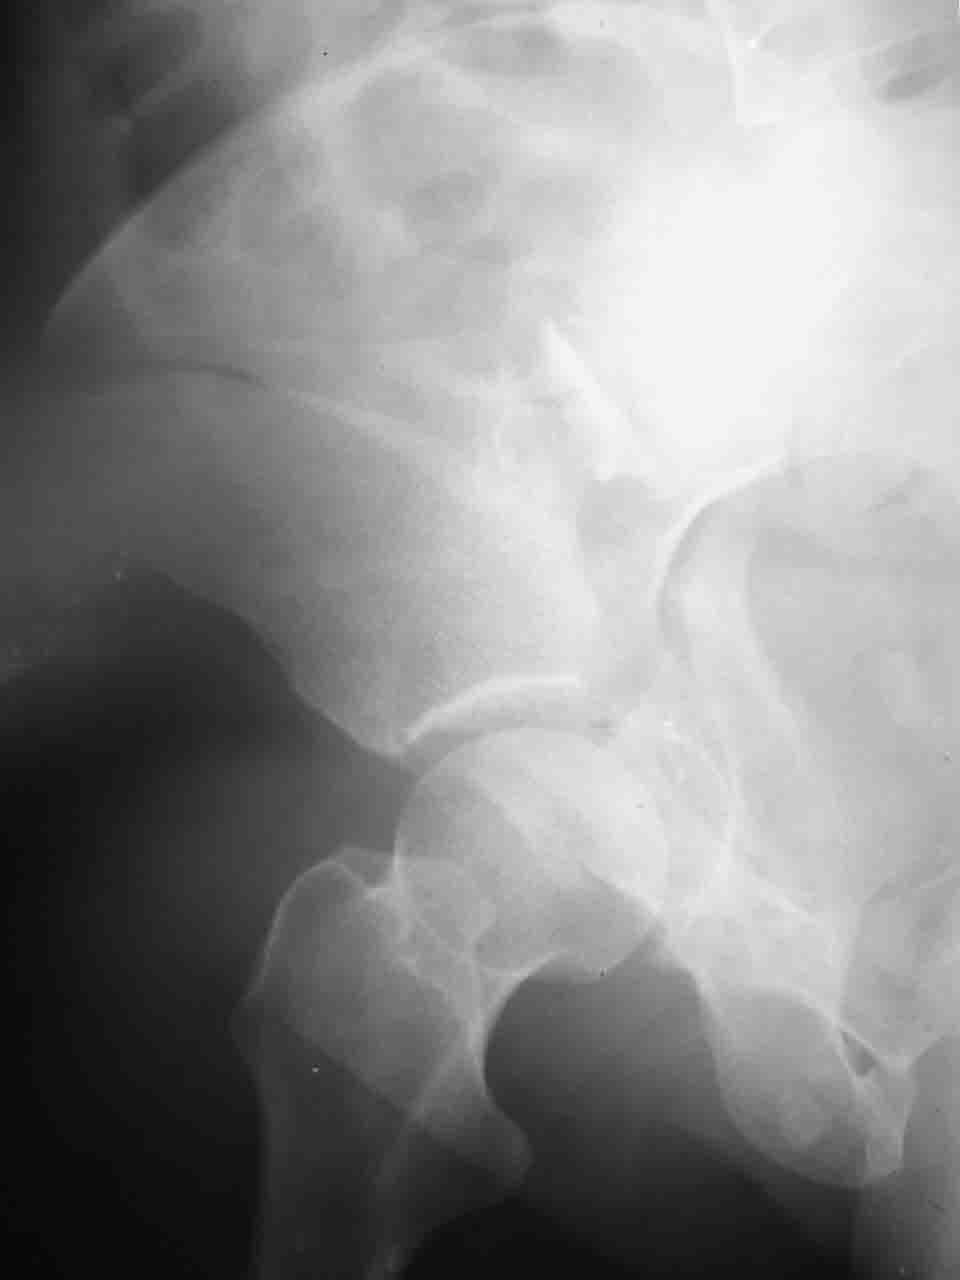

Интерес к реконструкции вертлужной впадины у меня появился довольно-таки давно, но до недавнего времени как-то не ощущалась готовность к практической реализации, а местный подход достаточно консервативен - перелом срастется,

а далее будет видно. Такую точку зрения я не разделяю, поэтому через конференции,ортофорум и свои случаи пытаюсь практически и теоретически *продвинуть* для себя тему реконструкции вертлужной впадины.

Логика подсказывает, что все-таки лучше иметь анатомически полноценную впадину, хотя ранее упоминалось состояние вторичной конгруэнтности и одно наблюдение у меня есть, когда у больного с полностью нарушенной анатомией впадины и подвывихом головки бедра кзади и кверху боли отсутствовали при относительно достаточном для стиля жизни больного объёме движений. Но это только одно наблюдение и кроме перелома впадины у этогобольного была и тяжелая ЧМТ в анамнезе. Основываясь на формулировке структуры ацетабулюм Э. Летурнеля - как перевернутой буквы Y, впадина для полноценной функции сустава должна иметь сферичность, соответствующую размеру головки бедра и если один из компонентов в дефиците, то функциональные последствия рано или поздно проявятся.